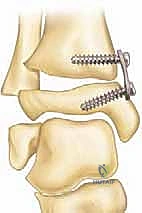

كيف تعمل التقنية؟

يشبه الأمر تماماً تقويم الأسنان. يقوم الأستاذ الدكتور محمد هطيف بتركيب شريحة معدنية صغيرة جداً (تُعرف بشريحة الـ 8-Plate أو شريحة الشد) على الجانب الداخلي (الأسرع نمواً) من مركز النمو في أسفل عظمة الساق. هذه الشريحة تعمل كمكبح لطيف؛ فهي تبطئ النمو في الجانب الداخلي، بينما تسمح للجانب الخارجي بالاستمرار في النمو بشكل طبيعي. بمرور الأشهر، وبفضل استمرار نمو الطفل، "يُعدّل" الكاحل نفسه تدريجياً ويستقيم محوره تماماً.

الخطوة الرابعة: تثبيت الشريحة (8-Plate)

بمهارة فائقة، يقوم الدكتور هطيف بوضع الشريحة المعدنية المصنوعة من التيتانيوم الطبي النقي فوق مركز النمو. يتم تثبيت الشريحة باستخدام مسمارين صغيرين؛ أحدهما فوق خط النمو والآخر تحته. هذه المسامير لا تخترق مركز النمو نفسه، مما يضمن عدم تدميره.